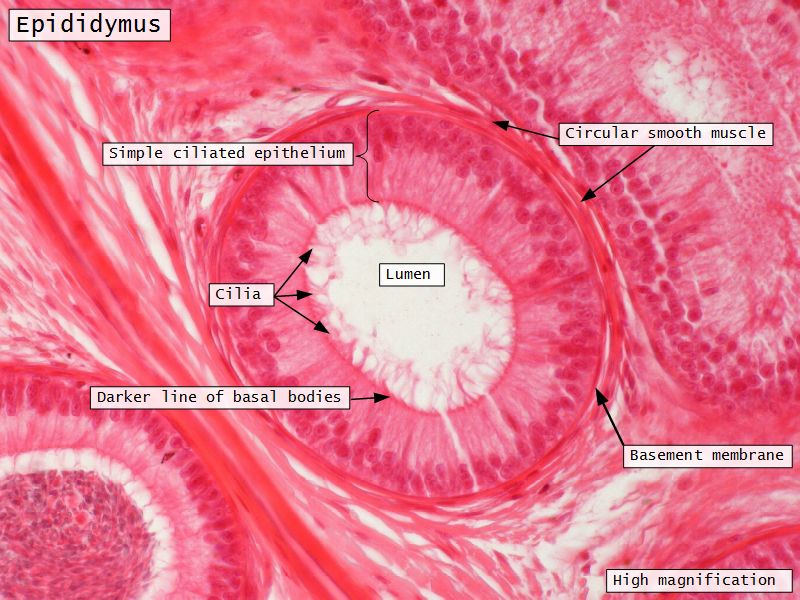

Epididymus

- Long convoluted duct

- With fibrous covering

- Inside visceral layer of tunica vaginalis testis

Epididymus

- Simple ciliated columnar epithelium

- Tall ciliated cells

- Elongated nuclei away from BM

- Low absorptive cells

- Spherical nuclei close to BM

- Surrounded circular smooth muscle